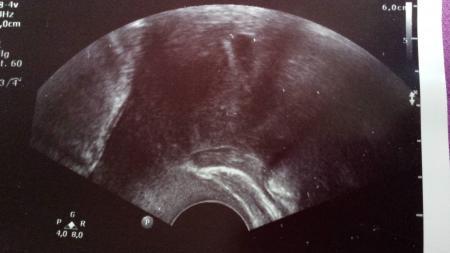

Hallo, Das ist doch ganz normal. Hänge dir mal ein Bild von 5+1 an. Also auch nur eine Fruchthöhle. Mein Sohn ist jetzt 3 Jahre und sitzt neben mir :) In meiner jetzigen Schwangerschaft war es genauso Alles gute, beim nächsten Termin wird man mehr sehen können!

Bild zu

Huhu schau mal :) das War mein US in der 5. Woche ca... ich hab nun Mittwoch wieder ein termin aber beunruhigt bin ich ehrlich gesagt nicht, meine FÄ sagte das sieht alles normal aus und bein nächsten mal sehe man schon mehr :) ..